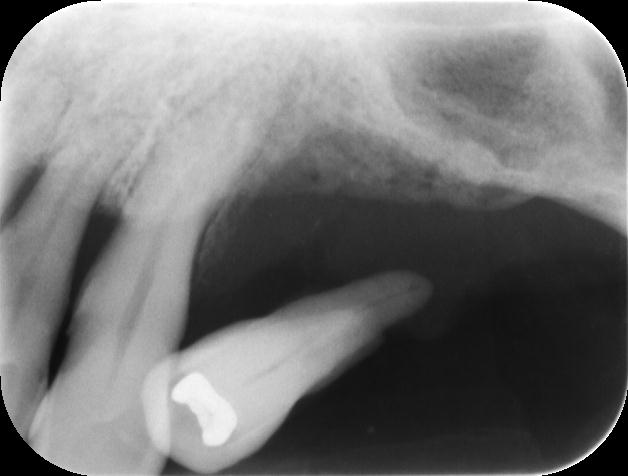

歯がグラグラするので抜歯して欲しいとの事で来院されました。

レントゲンでは歯が浮いた状態です。

今回は歯周病でこのようなレントゲン像を呈していましたが、悪性腫瘍でもこのようなレントゲン像を呈する事があり注意が必要です。